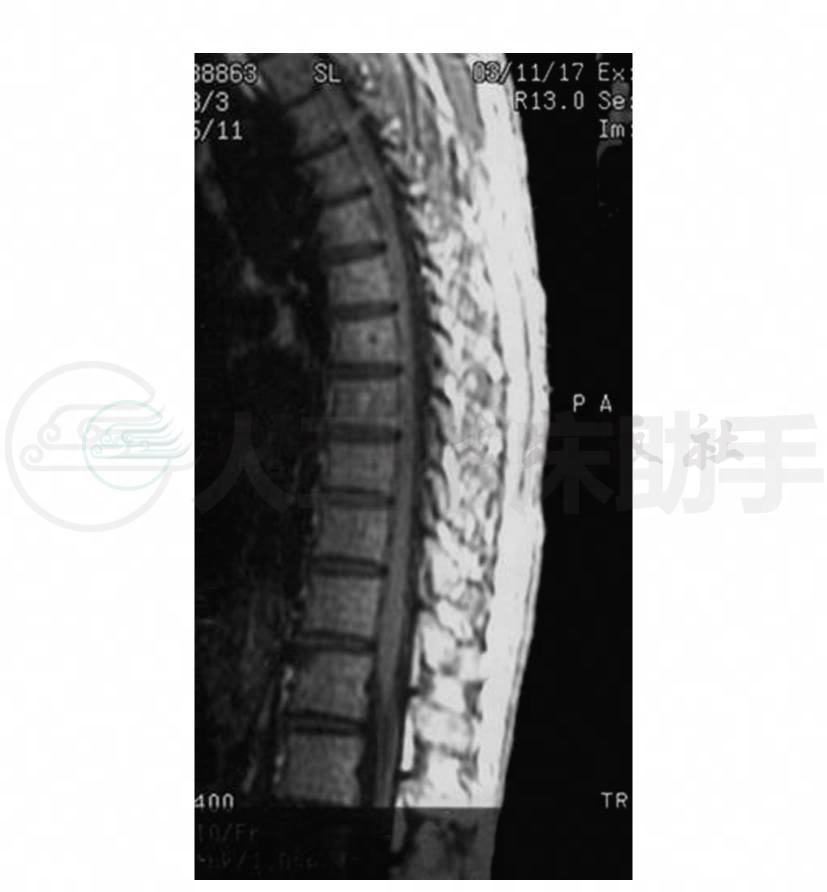

8.胸椎MRI(1998-12-25)胸3以下脊髓稍增粗,脊髓内呈T1WI稍低、T2WI高信号,边缘模糊,脊髓与蛛网膜间不规则,椎管无明显狭窄,椎体大小,形态及附件未见异常改变(图1,图2)。增强扫描(1999-1-8)示“上述病灶略有增强,考虑胸段脊髓之改变以脊髓炎可能性大,不除外星形细胞瘤”。

图2 胸椎MRI矢状位T2WI示胸3以下脊髓稍增粗,脊髓内异常高信号,边缘模糊,脊髓后脑脊液信号有许多圆点样流空信号